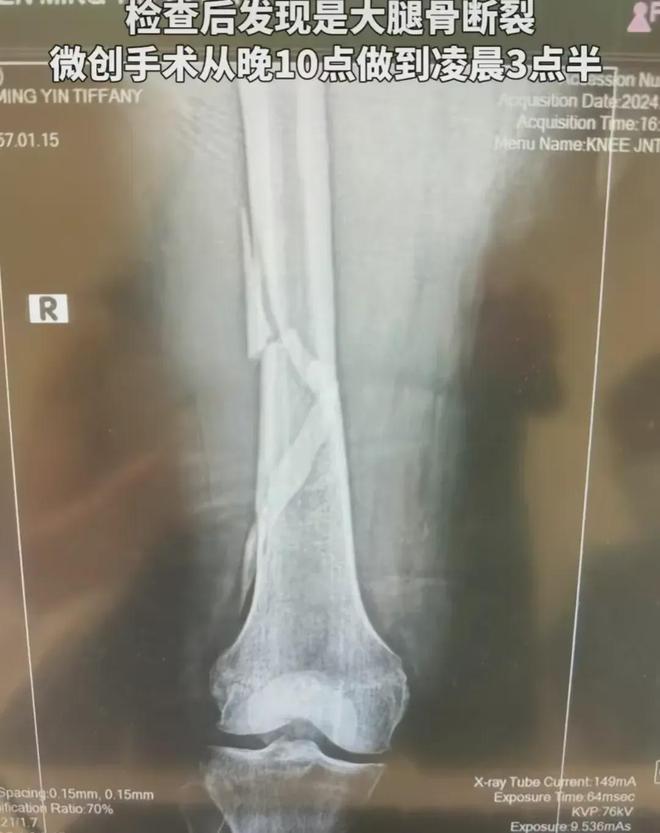

影像学检查:如X光、CT或MRI,以确定是否有骨折、炎症或其他结构性问题。

手术治疗:在严重骨折或关节损伤的情况下,可能需要进行手术治疗。